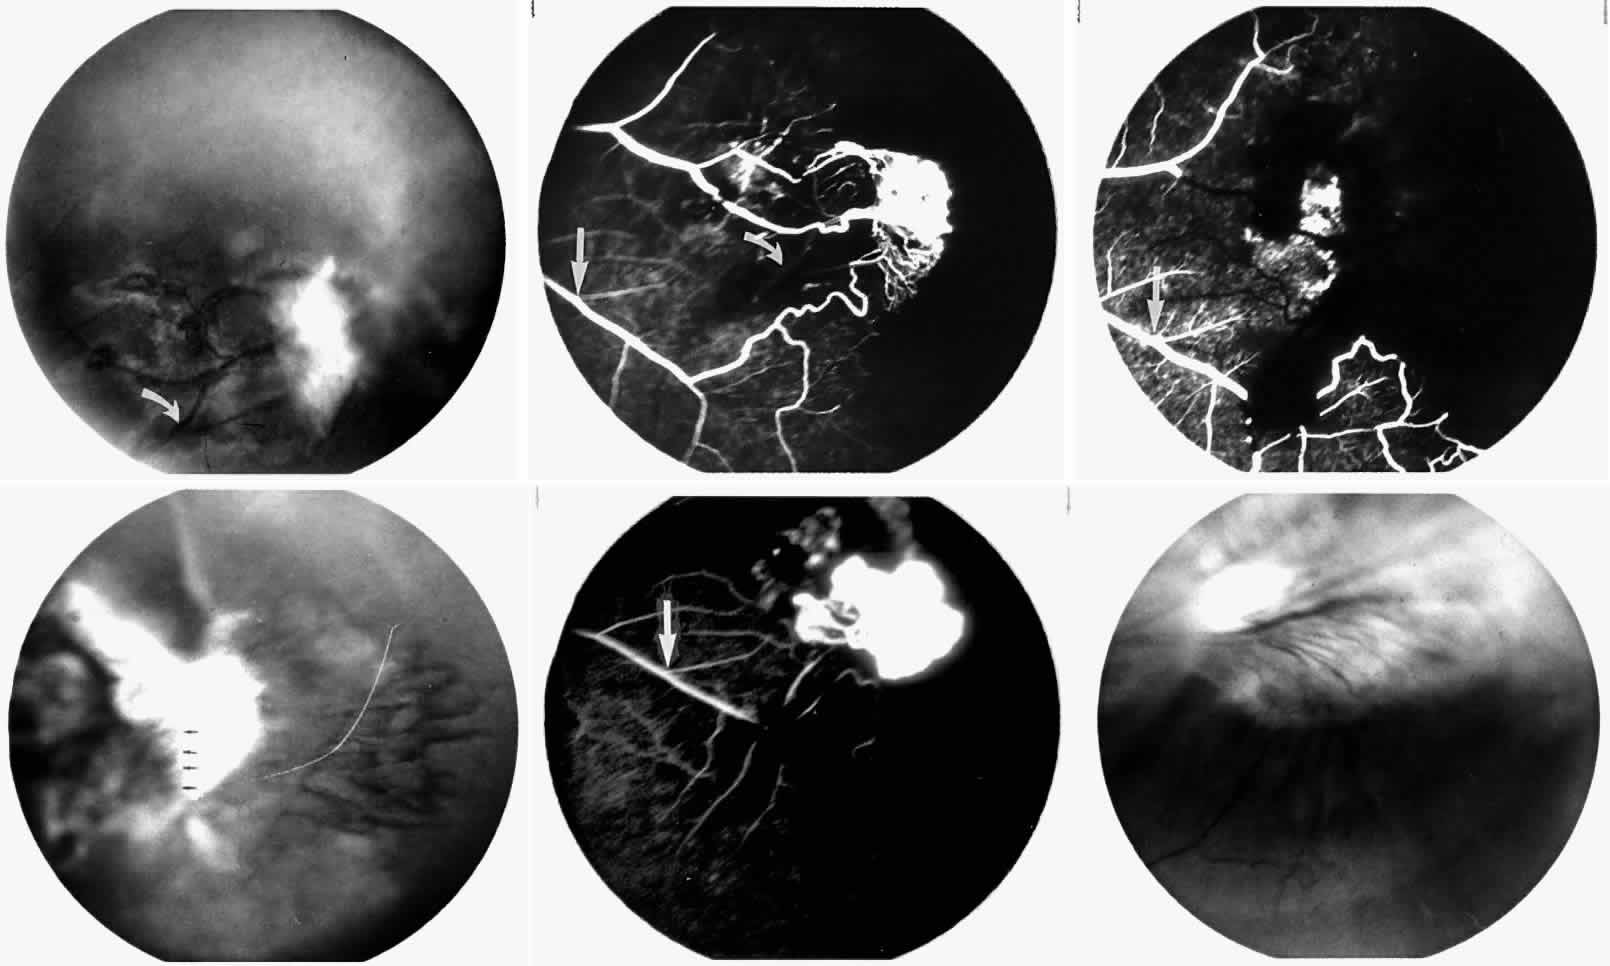

STAGE III: PRERETINAL NEOVASCULARIZATION (PROLIFERATIVE SICKLE RETINOPATHY). “Sea fan”-shaped neovascularization typically develops on the venular side of an arteriolar-venular anastomosis, mimicking the normal development of retinal capillaries (Fig. 24).125 A lowered oxygen tension and angiogenic factors released on the venular side may be the stimulus for neovascular growth.125,126 In most instances, the direction of growth is toward the ora serrata, from the perfused retina toward the nonperfused retina. Presumably, this represents an abortive attempt to revascularize the nonperfused retina, initiated by vasoproliferative factors.

Fig. 24. A. Photograph of the peripheral retina, demonstrating several small fibroglial membranes. B. Fluorescein angiogram corresponding to A, showing multiple arteriolar-venular anastomoses with early sea fan formation. C. Photograph of the same area 2 years later demonstrates more fibroglial membranes. D. Fluorescein angiogram corresponding to C shows new sea fans caused by an arteriolar-venular anastomosis (curved arrow). Large arrow (A through D) identifies corresponding arteriolar bifurcation.

The characteristic neovascular lesions of PSR are called sea fans because they resemble the marine invertebrate Gorgonia flabellum.70 They tend to occur more commonly in the temporal periphery, but they have been reported to occur in the temporal macula in the presence of extensive nonperfusion.130,133 Initially they grow on the surface of the retina, but they often become elevated into the vitreous and adhere to a partially detached posterior hyaloid.114 It may be difficult to visualize small sea fans ophthalmoscopically; however, fluorescein angiography clearly demonstrates leakage of dye into the vitreous (Fig. 25). The feeding arteriole is usually more tortuous than the draining venule (Fig. 26). Early on, the neovascular lesion is fed by a single arteriole and drained by a single venule, but with time, additional arterioles and venules become arborized within the lesion (Fig. 27).129 Growth of the sea fan often occurs circumferentially, rather than radiallyÜmh- 1Ý, toward the ora serrata. Progressive circumferential growth may lead to neovascular lesions extending around the entire periphery. As it matures, a white fibroglial mantle often covers the neovascular tissue (Color Plate 2B).

Fig. 25. Fluorescein angiogram of early proliferative sickle retinopathy arising from an arteriolar-venular anastomosis in an area of irregular peripheral capillary border. Note that this area of qualitatively abnormal peripheral capillary border is in the same eye with a qualitatively normal peripheral retinal vasculature, as demonstrated in Figure 23.

Fig. 26. A. Arterial filling phase of the fluorescein angiogram of a sea fan demonstrates tortuosity of the feeding arteriole. B. Early arteriolar-venular filling phase demonstrates straightening of the draining venule. Note that this sea fan is adjacent to the qualitatively normal peripheral retinal vasculature demonstrated in Figure 23.

Fig. 27. A. Photograph of sea fan neovascularization with hemorrhages at the margins and a white line demarcating perfused and nonperfused retina. B. Fluorescein angiogram shows multiple feeding arterioles and draining venules.